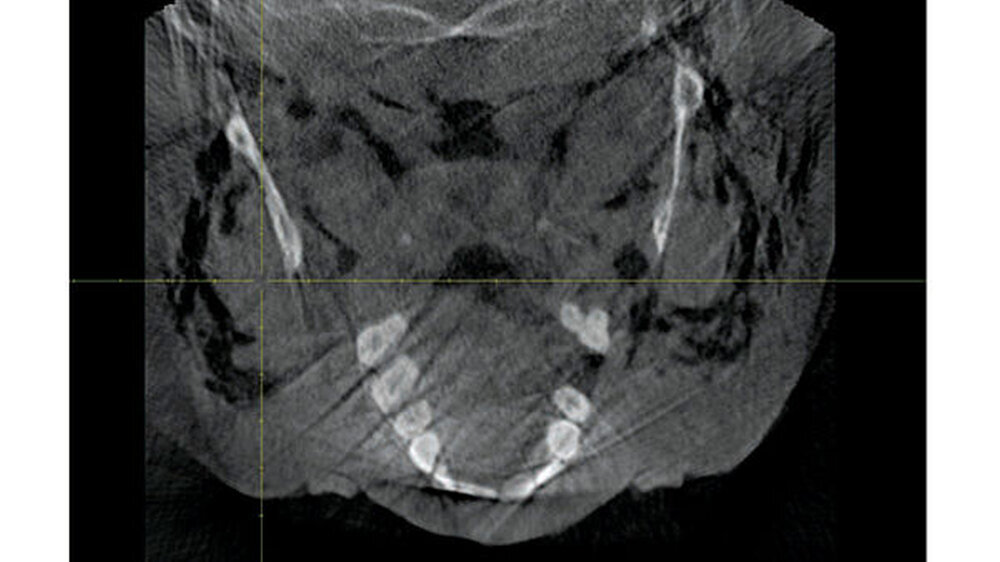

Zum Ausschluss einer Mittelgesichtsfraktur bei palpatorischem Weichteilemphysem erfolgte zur weiteren Diagnostik eine DVT-Aufnahme. Es zeigten sich keine Frakturen im Bereich des Mittelgesichts oder der Kiefer. Jedoch kam in der DVT-Bildgebung sowie der OPT-Optik ein massives Weichgewebeemphysem zur Darstellung (Abbildungen 2 bis 5).

Weiterhin wird deutlich, dass bei in aller Regel doch sehr eingeschränkter Beurteilbarkeit von Weichgewebe im DVT in diesem speziellen Fall eine weiterführende Diagnostik und Therapie eingeleitet werden konnte.

Das Emphysem war initial im DVT so eindrucksvoll sichtbar, dass es trotz fehlender klinischer Symptomatik im Thoraxbereich des Patienten, schwieriger Anamnese und blander zweidimensionaler Bildgebung der Lunge (RÖ-Thorax) der Faktor für eine weitere dreidimensionale Bildgebung (CT-Thorax) war, der letztendlich die Verdachtsdiagnose sicherte.

Zur Frakturdiagnostik im Mittelgesichtsbereich eignet sich das DVT sehr gut, außerdem ist die freie Luft des Emphysems im undifferenzierten Weichgewebe gut darstellbar.